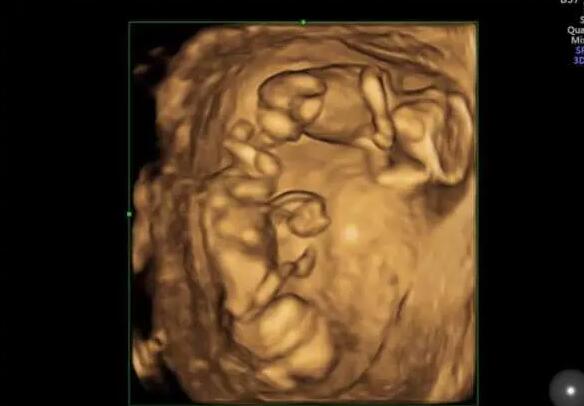

医院简介:目前专业技术人员18人,其中生殖临床医师6人(包括1名男科临床医师),实验室人员5人,护理人员7人。硕士研究生9人。中心由生殖医学临床(包括男科),生殖医学实验室,生殖医学病房三部分组成。生殖医学科是严格按照卫生部[2003]176号文件和省卫生厅的规划要求组建的。成立了院生殖医学伦理委员会,在伦理委员会的监督和指导下开展工作。